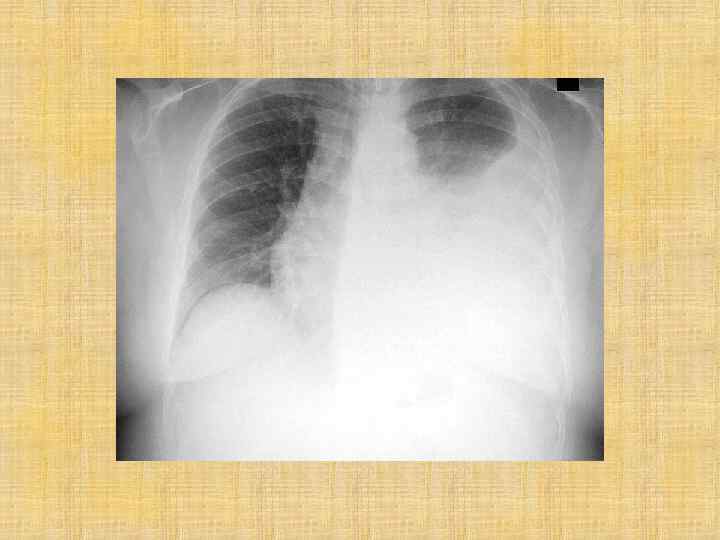

Рентгенография грудной клетки Эксудативный плеврит левосторонний Пневмония, осложненная внутрилегочной деструкцией Буллезная форма деструктивной пневмонии Очаговая пневмония

Пневмония правосторонняя нижнедолевая